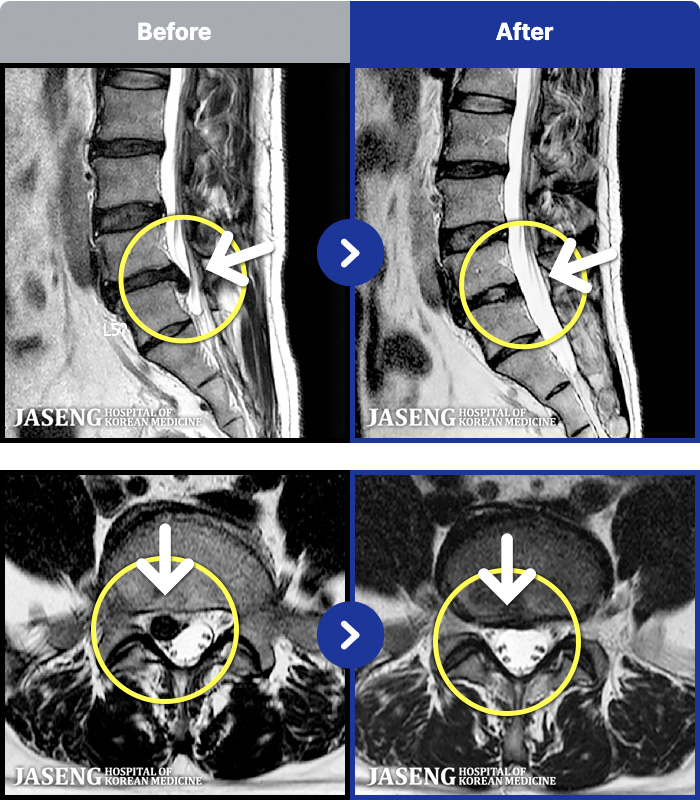

- MRI ġ

MRI ġ

191 MRI ũ ʸ Ȯϼ.

[Կñ:22.07.16~26.03.17]

[_㸮ũ] 㸮 ٸ ϰ ϻȰ Ұ߽ϴ.